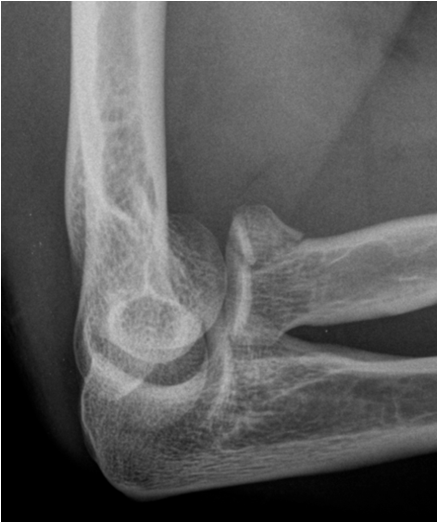

17.3.3. Dislocation and Subluxation

When the range of normal relationships for a particular joint is slightly exceeded, it is called a subluxation. When it is grossly exceeded, and the articulating structures are not in contact any more, it is called a dislocation. Joints most frequently affected by a luxation are shoulder, elbow, ankle, hip, and interphalangeal joints. Luxation will usually cause capsule and ligament disruption with soft tissue swelling and loss of fat planes. Associated avulsion fractures are frequently seen. As in fracture imaging exposure in two perpendicular planes are required to correctly visualize and describe a luxation or dislocated fracture.

Fig. 12. A) Complete dislocation with contraction in the elbow joint. Ulna and radius are both dislocated and dorsally displaced. B.) Anterior and inferior dislocation of the humerus.